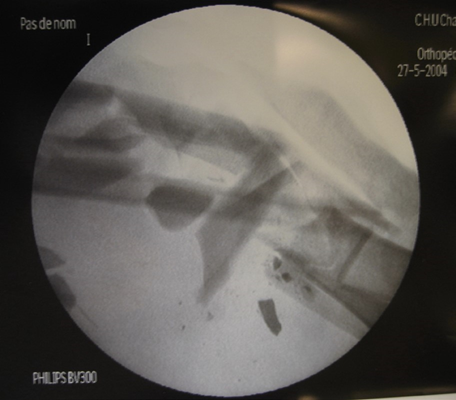

Figure 2 : X-ray imaging shows a multifragmented fracture of the tibia and fibula.

Figure 3 : “Reduction” and osteosynthesis by tibio-calcaneal external fixator was immediately performed.